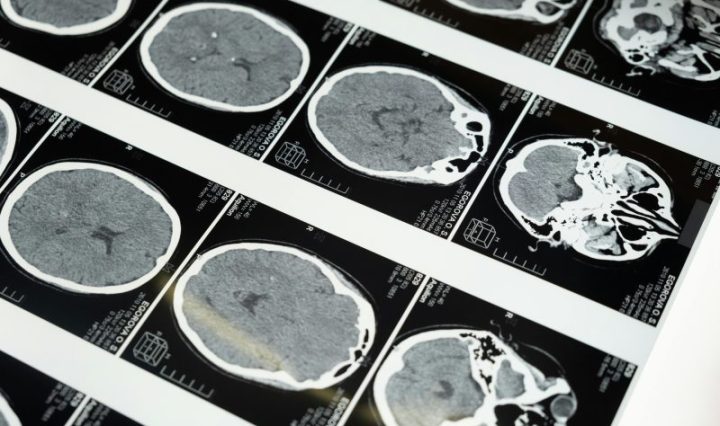

#MayoClinic #gliomas #cáncer #NoticiasIbo Investigadores de Mayo Clinic identificaron una posible nueva forma de monitorear la progresión de los gliomas, uno de los tipos más agresivos de cáncer de cerebro. El estudio de viabilidad sugiere que un análisis de sangre personalizado, adaptado al ADN … Continúa leyendo Investigadores de Mayo Clinic revelan un enfoque personalizado para el monitoreo del cáncer de cerebro